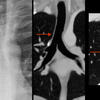

vessesls MR

Date: 02/25/2013

Views: 3222